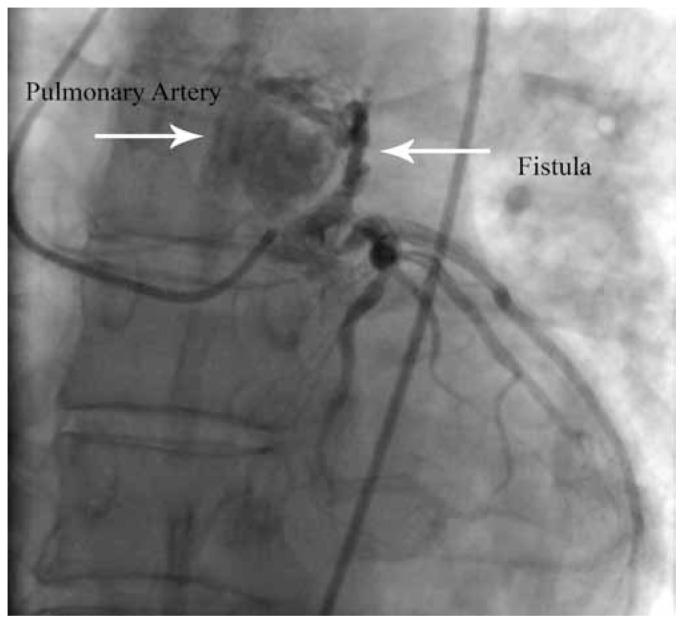

Clinical features of coronary artery fistula.

J Tehran Heart Cent. 2011 Summer;6(3):158-62. Epub 2011 Aug 31.